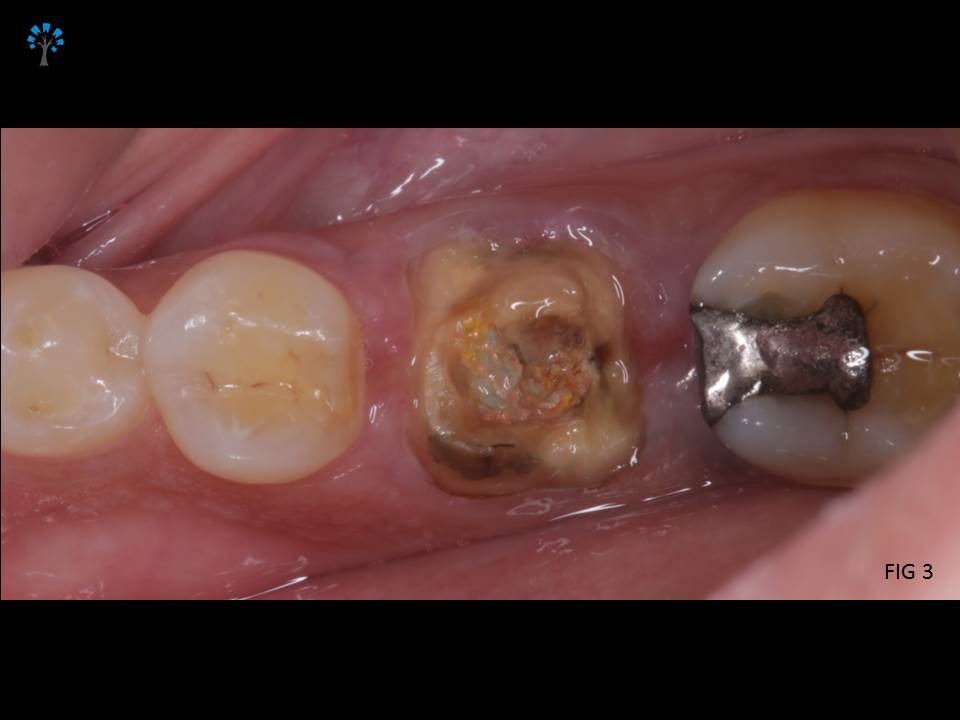

An elderly patient reported with a dislodged gold crown.

Examination revealed fracture of the distal portion of the tooth (Fig 1,4).

Given the medical status of the patient and based on certain existing favorable anatomic features with diagnosis from the Intra oral xray (Fig 2), we decided to retain the tooth and restore it.

PREOPERATIVE VIEW